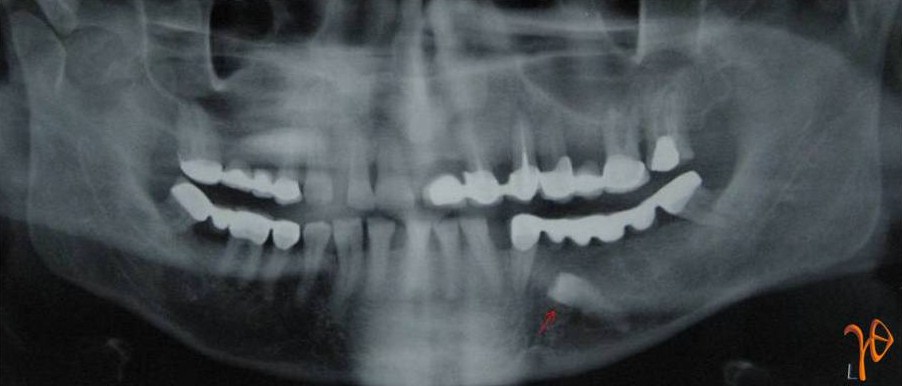

Εικ. 9: Πανοραμική ακτινογραφία στην οποία απεικονίζεται ο υπεράριθμος προγόμφιος (βέλος). Ο 35-χρονος ασθενής ανέφερε ήπιο άλγος στη σύστοιχη προγομφιακή περιοχή.

Εικ. 11: Πανοραμική ακτινογραφία στην οποία απεικονίζεται ο υπεράριθμος προγόμφιος (βέλος) του 55-χρονου ασθενή. Παρότι ασυμπτωματικός, ο υπεράριθμός αφαιρέθηκε λόγω προγραμματισμού τοποθέτησης οδοντικών εμφυτευμάτων στην περιοχή.